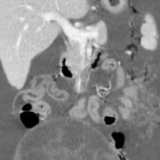

面对这一复杂罕见病例,中南大学湘雅三医院妇科主任徐大宝与肖松舒教授评估考虑为卵巢恶性生殖细胞肿瘤晚期可能性大,立即启动肿瘤多学科会诊,邀请呼吸科、外科、麻醉科、肿瘤科、ICU等多学科专家讨论,制定适宜该青春期女性患者的个体化、最优化手术和围术期处理方案。经过术前多次放胸水改善肺功能和完善PET-ET全面评估等处理后,6月6日在麻醉科主任段开明的保驾护航下由易水晶副教授主刀手术。术中见盆腔大量血性腹水约2000ml,右侧卵巢见一20cm囊实性肿物(可见破口),子宫直肠陷凹多发转移病灶,快速病检证实为未成熟畸胎瘤并转移。团队精细操作,行保留生育功能手术,盆腹腔减瘤R0。术后患者拔管后安返妇科病房,并顺利完成HIPEC(肿瘤热灌注)治疗后出院。